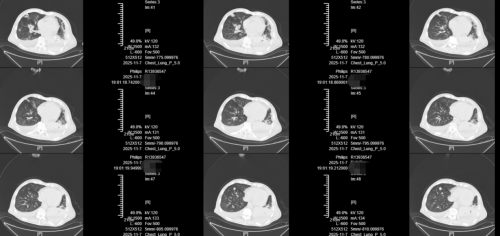

治疗前的胸部CT(11月7日):双肺散在炎变,考虑并有肺脓肿;双侧胸腔积液;左肺上叶、双肺下叶部分肺不张